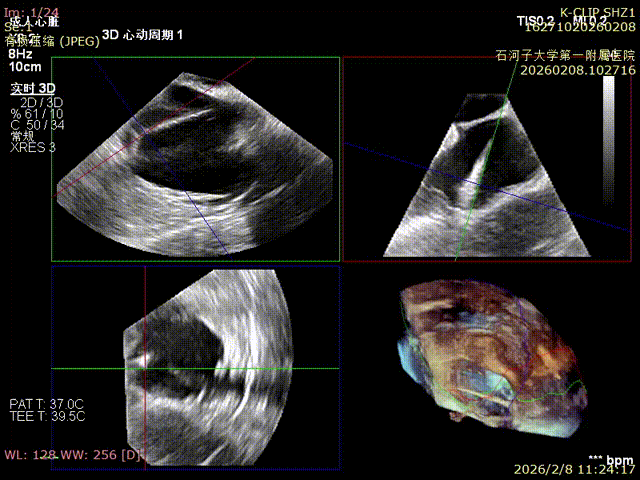

Comparison of preoperative reflux and postoperative reflux

Postoperative

Postoperative reflux

Immediate Postoperative Echocardiographic Assessment: Tricuspid regurgitation was reduced from preoperative grade 4+ to grade 1+, the annulus diameter was reduced to 6.15 cm², and the leaflet coaptation was satisfactory.

Preoperative annulus area: 11.5 cm²

Postoperative annulus area: 6.15 cm²